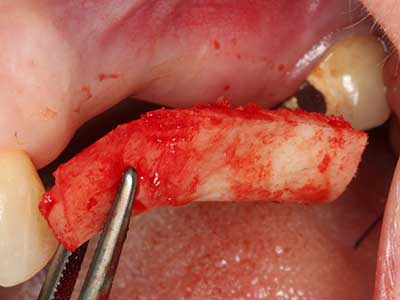

Fig. 3: La separación basal del bloque se ve facilitada con piezas dotadas de una angulación especial.

Fig. 4: Con la rasqueta ósea se obtienen virutas adicionales de hueso autógeno.

Fig. 5: Comprobación de las dimensiones del bloque en la zona de recepción.

En la extracción de bloques óseos la piezocirugía también presenta ventajas adicionales: Además de la alta precisión en la osteotomía que ya se ha descrito antes, se ha comprobado que el uso de los delgados insertos de sierra resulta especialmente cuidadosas con el hueso. Frente a esto, sobre todo cuando se usan las fresas de Lindemann, cabe esperar pérdidas en la extracción significativamente más altas debido al mayor grosor de la parte frontal del cabezal (Lakshmiganthan, Gokulanathan et al. 2012). La separación basal que se necesita en particular en los injertos de bloque extraídos de forma retromolar se ve facilitada mediante sierras perpendiculares especialmente previstas a tal fin, lo que permite considerar que la cirugía piezoeléctrica es un procedimiento preciso y seguro para la obtención de bloques de hueso en el área retromolar (Happe 2007) (fig. 1-12).